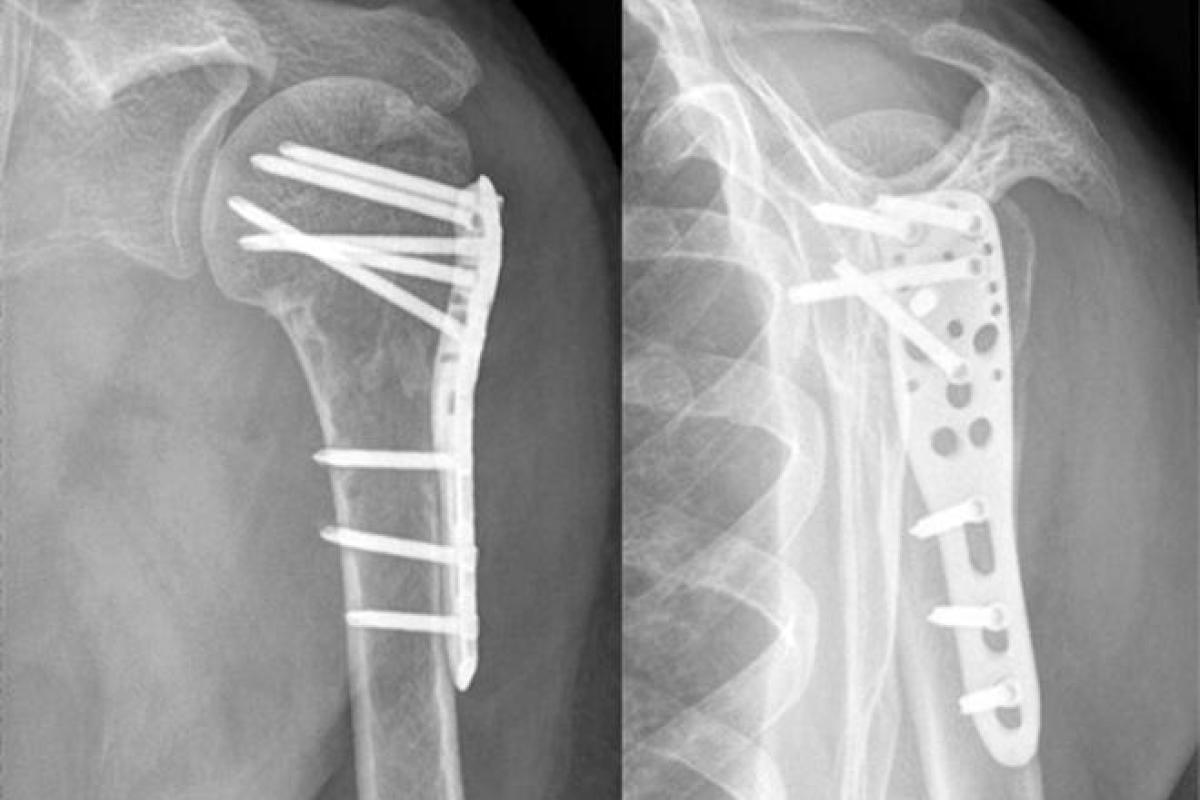

Что касается остеосинтеза предплечья, то существуют также различные варианты:

- Винты, болты и пластины металлического типа (винты устанавливаются непосредственно в костную ткань, пластины на костную поверхность);